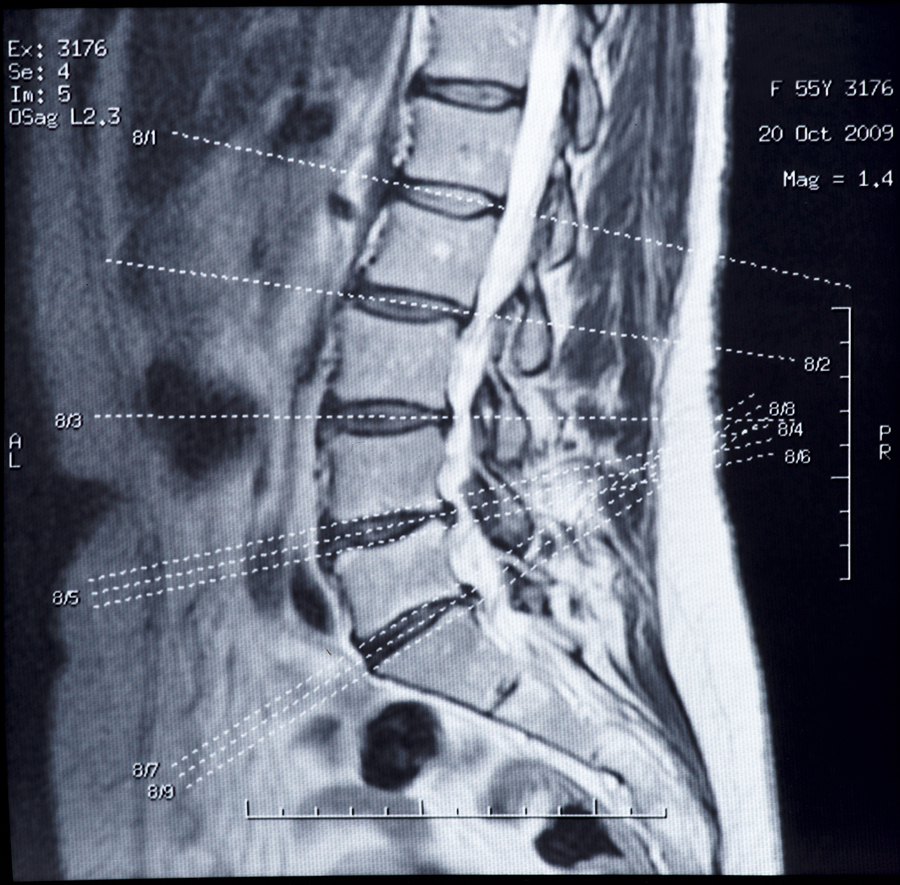

Patients with herniated discs experience back pain, leg pain (sciatica), and other symptoms caused by pressure on the spinal nerve roots.

The current analysis included eight-year follow-up data on 1,244 patients treated at 13 spine clinics across the United States. About 500 patients were randomly assigned to surgery (a procedure called discectomy) or nonsurgical treatment, although patients were allowed to “cross over” to the other treatment.